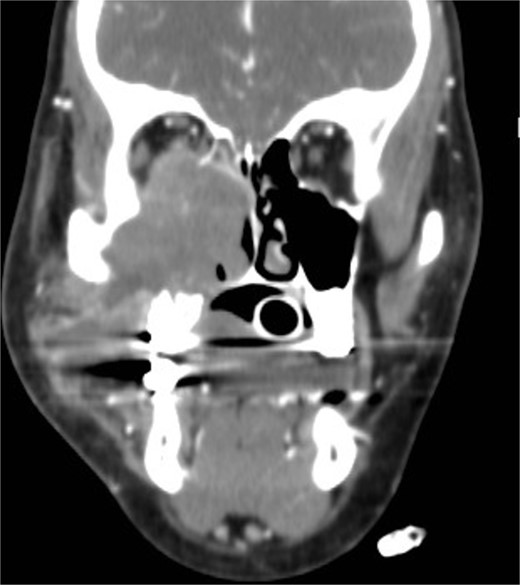

Isolated maxillary fungal ball

A 30-year-old lady presented to the clinic with a complaint of right facial pain, recurrent rhinorrhea with post-nasal discharge, nasal endoscopic examination was unremarkable. A non-contrast computed-tomography scan (NCCT) of the paranasal sinuses (Fig. 1) was suggestive of isolated right fungal maxillary fungal ball (FB). The patient underwent endoscopic sinus surgery (ESS) with (Fig. 2) right middle meatal antrostomy and removal of fungal debris. The patient was followed up regularly and remained symptom free.

Intra-operative endoscopic view (A) right middle meatal antrostomy showing fungal debris, (B) clean right maxillary sinus after removal of the debris.